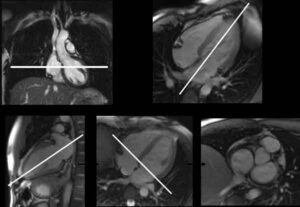

Cardiomiopatia da stress: subdola e più diffusa del previsto La risonanza magnetica mostra una sofferenza cardiaca anche in assenza di...